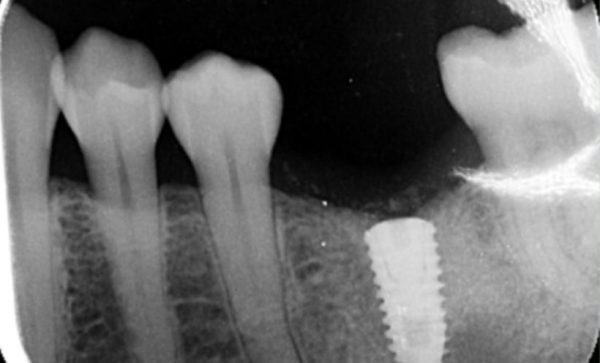

Case 25